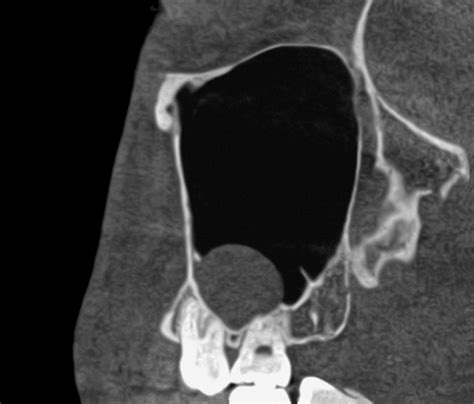

Cone Beam CT (CBCT) Offers a 3D view; essential for accurately measuring the size and location of the cyst.

Since these cysts rarely present with overt symptoms, diagnosis is almost always achieved through imaging. When your dentist or ENT specialist identifies a potential Cyst Sinus Maxillaris, they will use advanced imaging technology to differentiate it from other, more serious pathologies.

Diagnostic Procedures